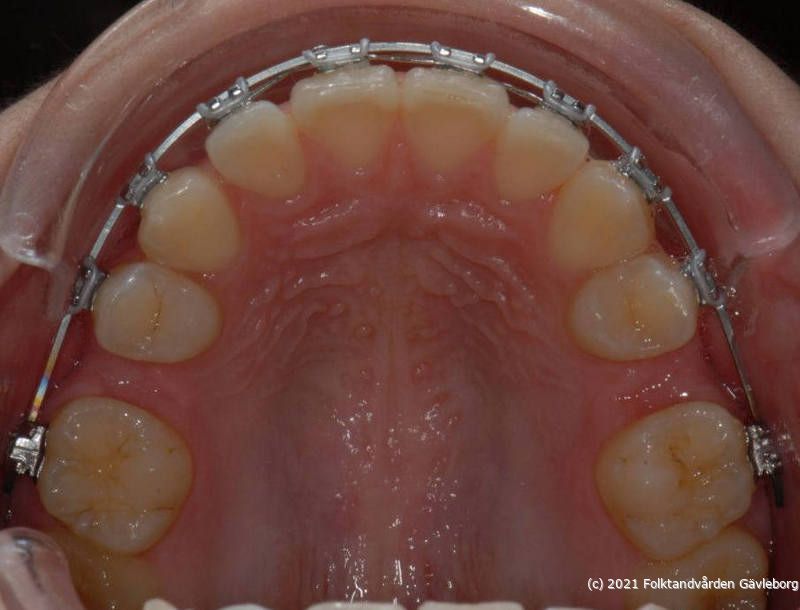

På ortodontiklinikerna diagnostiserar och behandlar vi bettfel på både barn och vuxna. Alla våra patienter kommer på remiss till oss. Vi behandlar bettfelen med fastsittande och avtagbar apparatur. Hos oss behandlas också de patienter som har avvikelser i käk- och ansiktsskelettet och som kräver tandreglering inför rekonstruktiv kirurgi. Vi har ett nära samarbete med allmäntandvård, privattandvård och övrig specialisttandvård i länet samt ett gott samarbete med Akademiska Sjukhuset i Uppsala när det gäller barn med olika syndrom och läpp-käk-gomdefekter. Våra specialistkliniker finns i Gävle och Hudiksvall.

Här nedan hittar du några exempel på vanligt förkommande behandlingar. Hittar du inget som passar det du vill visa, gå in på menyn ovan genom att föra musen över "Information". Navigera sedan till respektive apparatur. Klickar du på rubriken "Visa alla bilder" får du upp samtliga apparaturer som finns här.